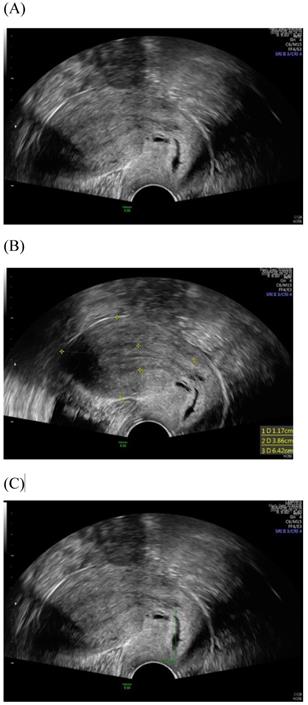

Figure 1

Transvaginal ultrasound image shows a longitudinal section of the uterus with normal cervix of the female aged 31-year-old. (A) Sagittal view (B) uterine size (C) cervical length.

Figure 2

Transabdominal ultrasound image shows a longitudinal section of the uterus with normal cervix of the female aged17-year-old. (A) Sagittal view (B) uterine size (C) cervical length.

Among imaging techniques for the evaluation of cervical cancer, ultrasound is faster, radiation-free, cheaper, noninvasive, no contrast medium required and more widely available than other imaging techniques [13]. Furthermore, advanced technologic developed in the field of ultrasound over the recent decades; image quality were improved. Transvaginal and transrectal high-frequency ultrasound, can give detailed images of the cervical tumor as the probe is positioned close to the tumor [13]. Anatomy features of longitudinal sections of the uterus with normal cervix by (TVUS) examination and transabdominal sonography are shown in Figures 1 and 2. Furthermore, Figure 3 showed vascularity detected by transvaginal Color Doppler in cervical cancer. Ultrasound may provide highly accurate information on detecting tumor presence evaluating local tumor extent if performed by ultrasound-trained gynecologists [6]. The experience of readers is also critical for correct pretreatment staging and assessment of response to treatment [6]. This review article attempted to present the most updated specific applications of ultrasound in cervical cancer.